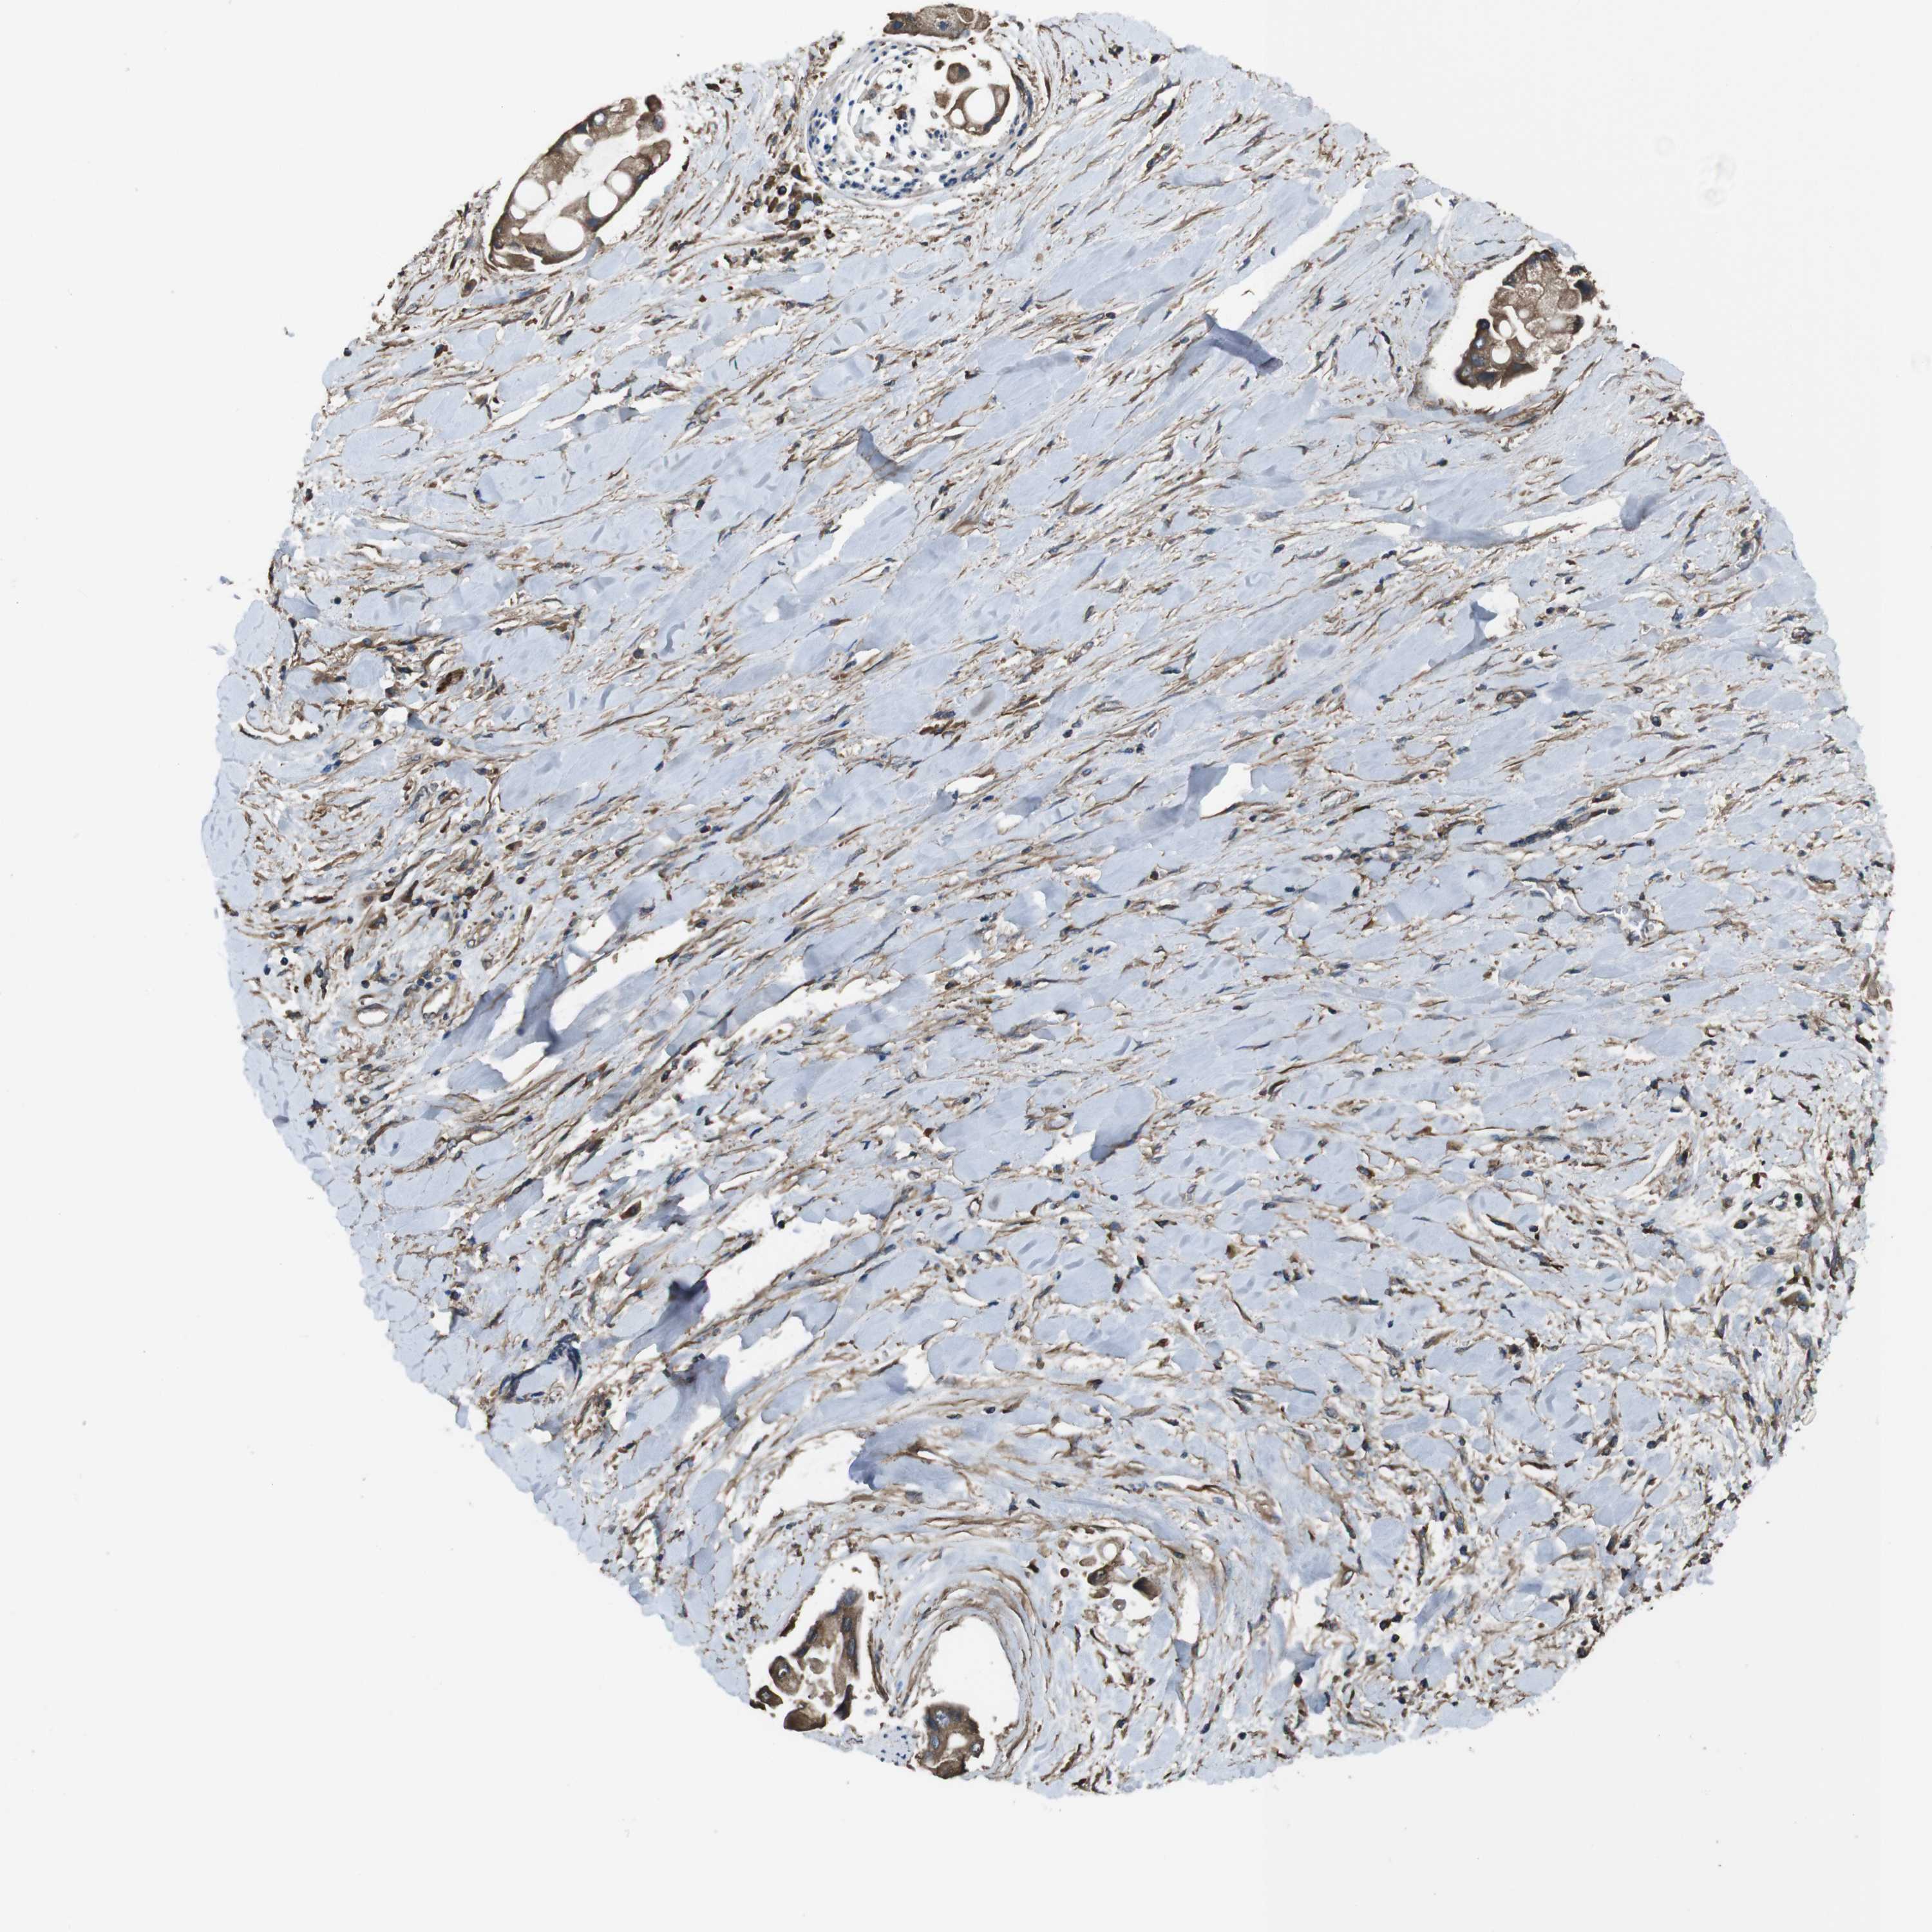

LIVER CANCER - Protein expressioni

A mouse-over function shows sample information and annotation data. Click on an image to view it in a full screen mode. Samples can be filtered based on level of antibody staining by selecting one or several of the following categories: high, medium, low and not detected. The assay and annotation is described here.

Note that samples used for immunohistochemistry by the Human Protein Atlas do not correspond to samples in the TCGA dataset.

Antibody stainingi

Antibody staining in the annotated cell types in the current human tissue is reported as not detected, low, medium, or high, based on conventional immunohistochemistry profiling in selected tissues. This score is based on the combination of the staining intensity and fraction of stained cells.

Each image is clickable and will lead to virtual microscopy that enables deeper exploration of all samples and also displays staining intensity scores, fraction scores and subcellular localization as well as patient and tissue information for each sample.

Antibody HPA014402

Staining

High

Medium

Low

Not detected

Intensity

Strong

Moderate

Weak

Negative

Quantity

>75%

75%-25%

<25%

None

Location

Nuclear

Cytoplasmic/membranous

Cytoplasmic/membranous,nuclear

Cholangiocarcinoma

Carcinoma, Hepatocellular, NOS